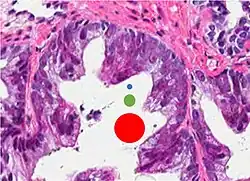

Microscopic characteristics

- Specific but relatively rare

- [notes 4]

- Collagenous micronodules[4]

- Glomerulations,[4] epithelial proliferations into one or more gland lumina, typically a cribriform tuft with a single attachment to the gland wall.[18]

- Perineural invasion.[4] It should be circumferential[18][notes 5]

- Angiolymphatic invasion[4]

- Extraprostatic extension [4]

-

Glomerulation.

- Relatively common and highly specific

- [4]

- Multiple nucleoli

- Eccentric nucleoli[4]

Acinar adenocarcinoma with multiple nucleoli. -

Acinar adenocarcinoma with double and eccentric nucleoli.

- Less specific findings.

- Mitoses (also seen in for example high-grade prostatic intraepithelial neoplasia (HGPIN) and prostate inflammation).[4]

- Prominent nucleoli[4]

- Intraluminal eosinophilic secretion[4]

- Intraluminal blue mucin[4]

Adenocarcinoma with two mitoses in reactive epithelium. -

Acinar adenocarcinoma with intraluminal blue mucin.